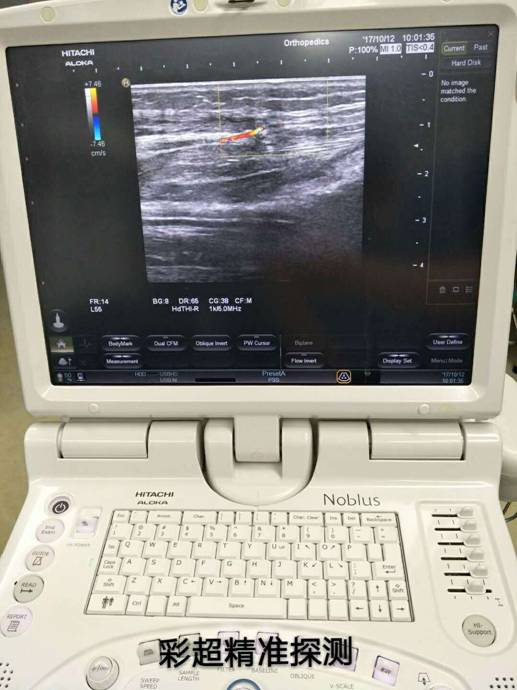

骨科根據(jù)患者骨折情況分別施行骨折復(fù)位+內(nèi)(外)固定術(shù),然后由燒傷整形科根據(jù)患者皮膚軟組織缺損情況,制定小腿穿支皮瓣轉(zhuǎn)移修復(fù)創(chuàng)面方案。為保證手術(shù)成功率,燒傷整形科會(huì)同超聲科由黃道遠(yuǎn)主任于術(shù)前利用彩超精準(zhǔn)的探測小腿術(shù)區(qū)的各個(gè)動(dòng)脈穿刺,并逐一標(biāo)記,再由燒傷整形科手術(shù)團(tuán)隊(duì)根據(jù)動(dòng)脈穿支的分布情況設(shè)計(jì)皮瓣,施行小腿穿支皮瓣轉(zhuǎn)移修復(fù)術(shù)。